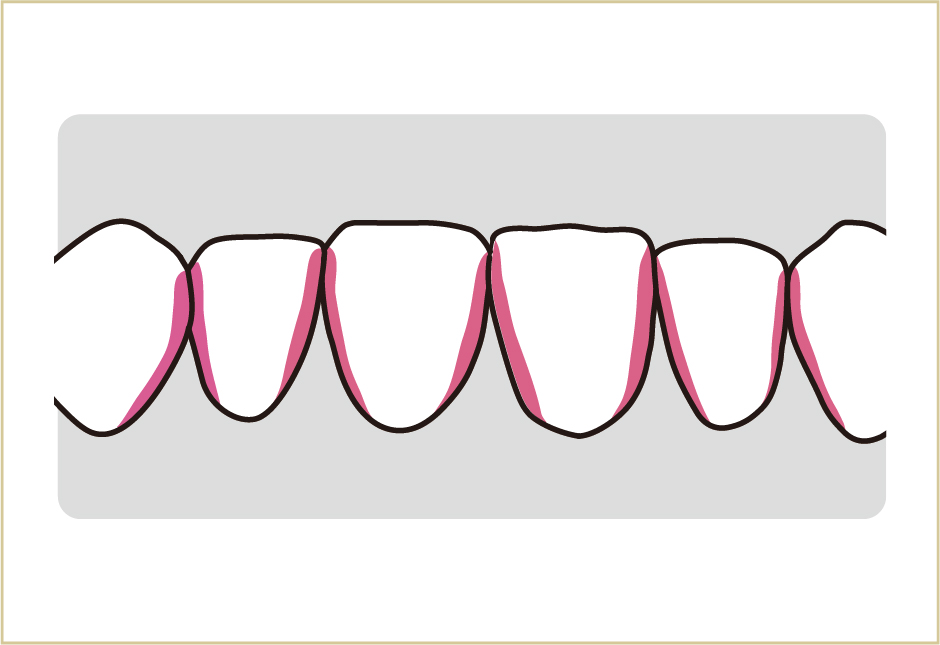

上の図は下の前歯を前から見た所です。このような歯と歯の間は歯ブラシでみがきにくく、虫歯にも歯周病にもなりやすい所です。

上の図は下の前歯を上から見下ろした所です。こうした、みがきにくい歯と歯の間の部分に、どうやって歯ブラシの毛先を入れるかが大事です。ここが虫歯になると表面が粗造になり、汚れがよりつきやすくなって、歯周病を誘発しやすい環境になるからです。

上の図は歯を横から見た所です。歯と歯肉の境目を、毎日しっかりきれいにすることが、歯周病予防につながります。